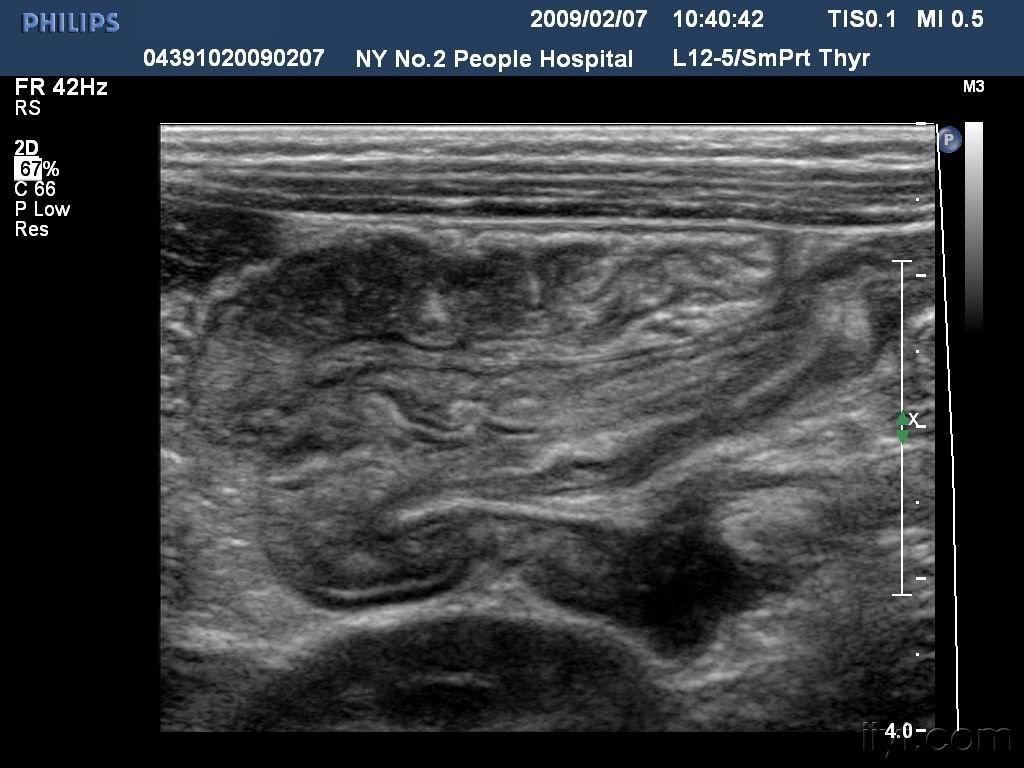

【读片】给你想要的鼠尾征---神经鞘瘤 2014-10-09 18:36 关注

鼠尾征